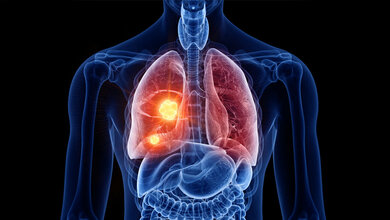

Nach wie vor ist Krebs eine häufige Diagnose. Etwa 500.000 Neuerkrankungen sind pro Jahr in Deutschland zu verzeichnen.

Doch auch bei der Diagnostik geht es mit Riesenschritten voran. Neben den neuen Möglichkeiten in der Bildgebung ist hier beispielsweise Liquid Biopsy ein Schlagwort. Die Nukleinsäureanalytik zum Nachweis von Tumorzellen und Tumor-DNA sorgt für Furore.